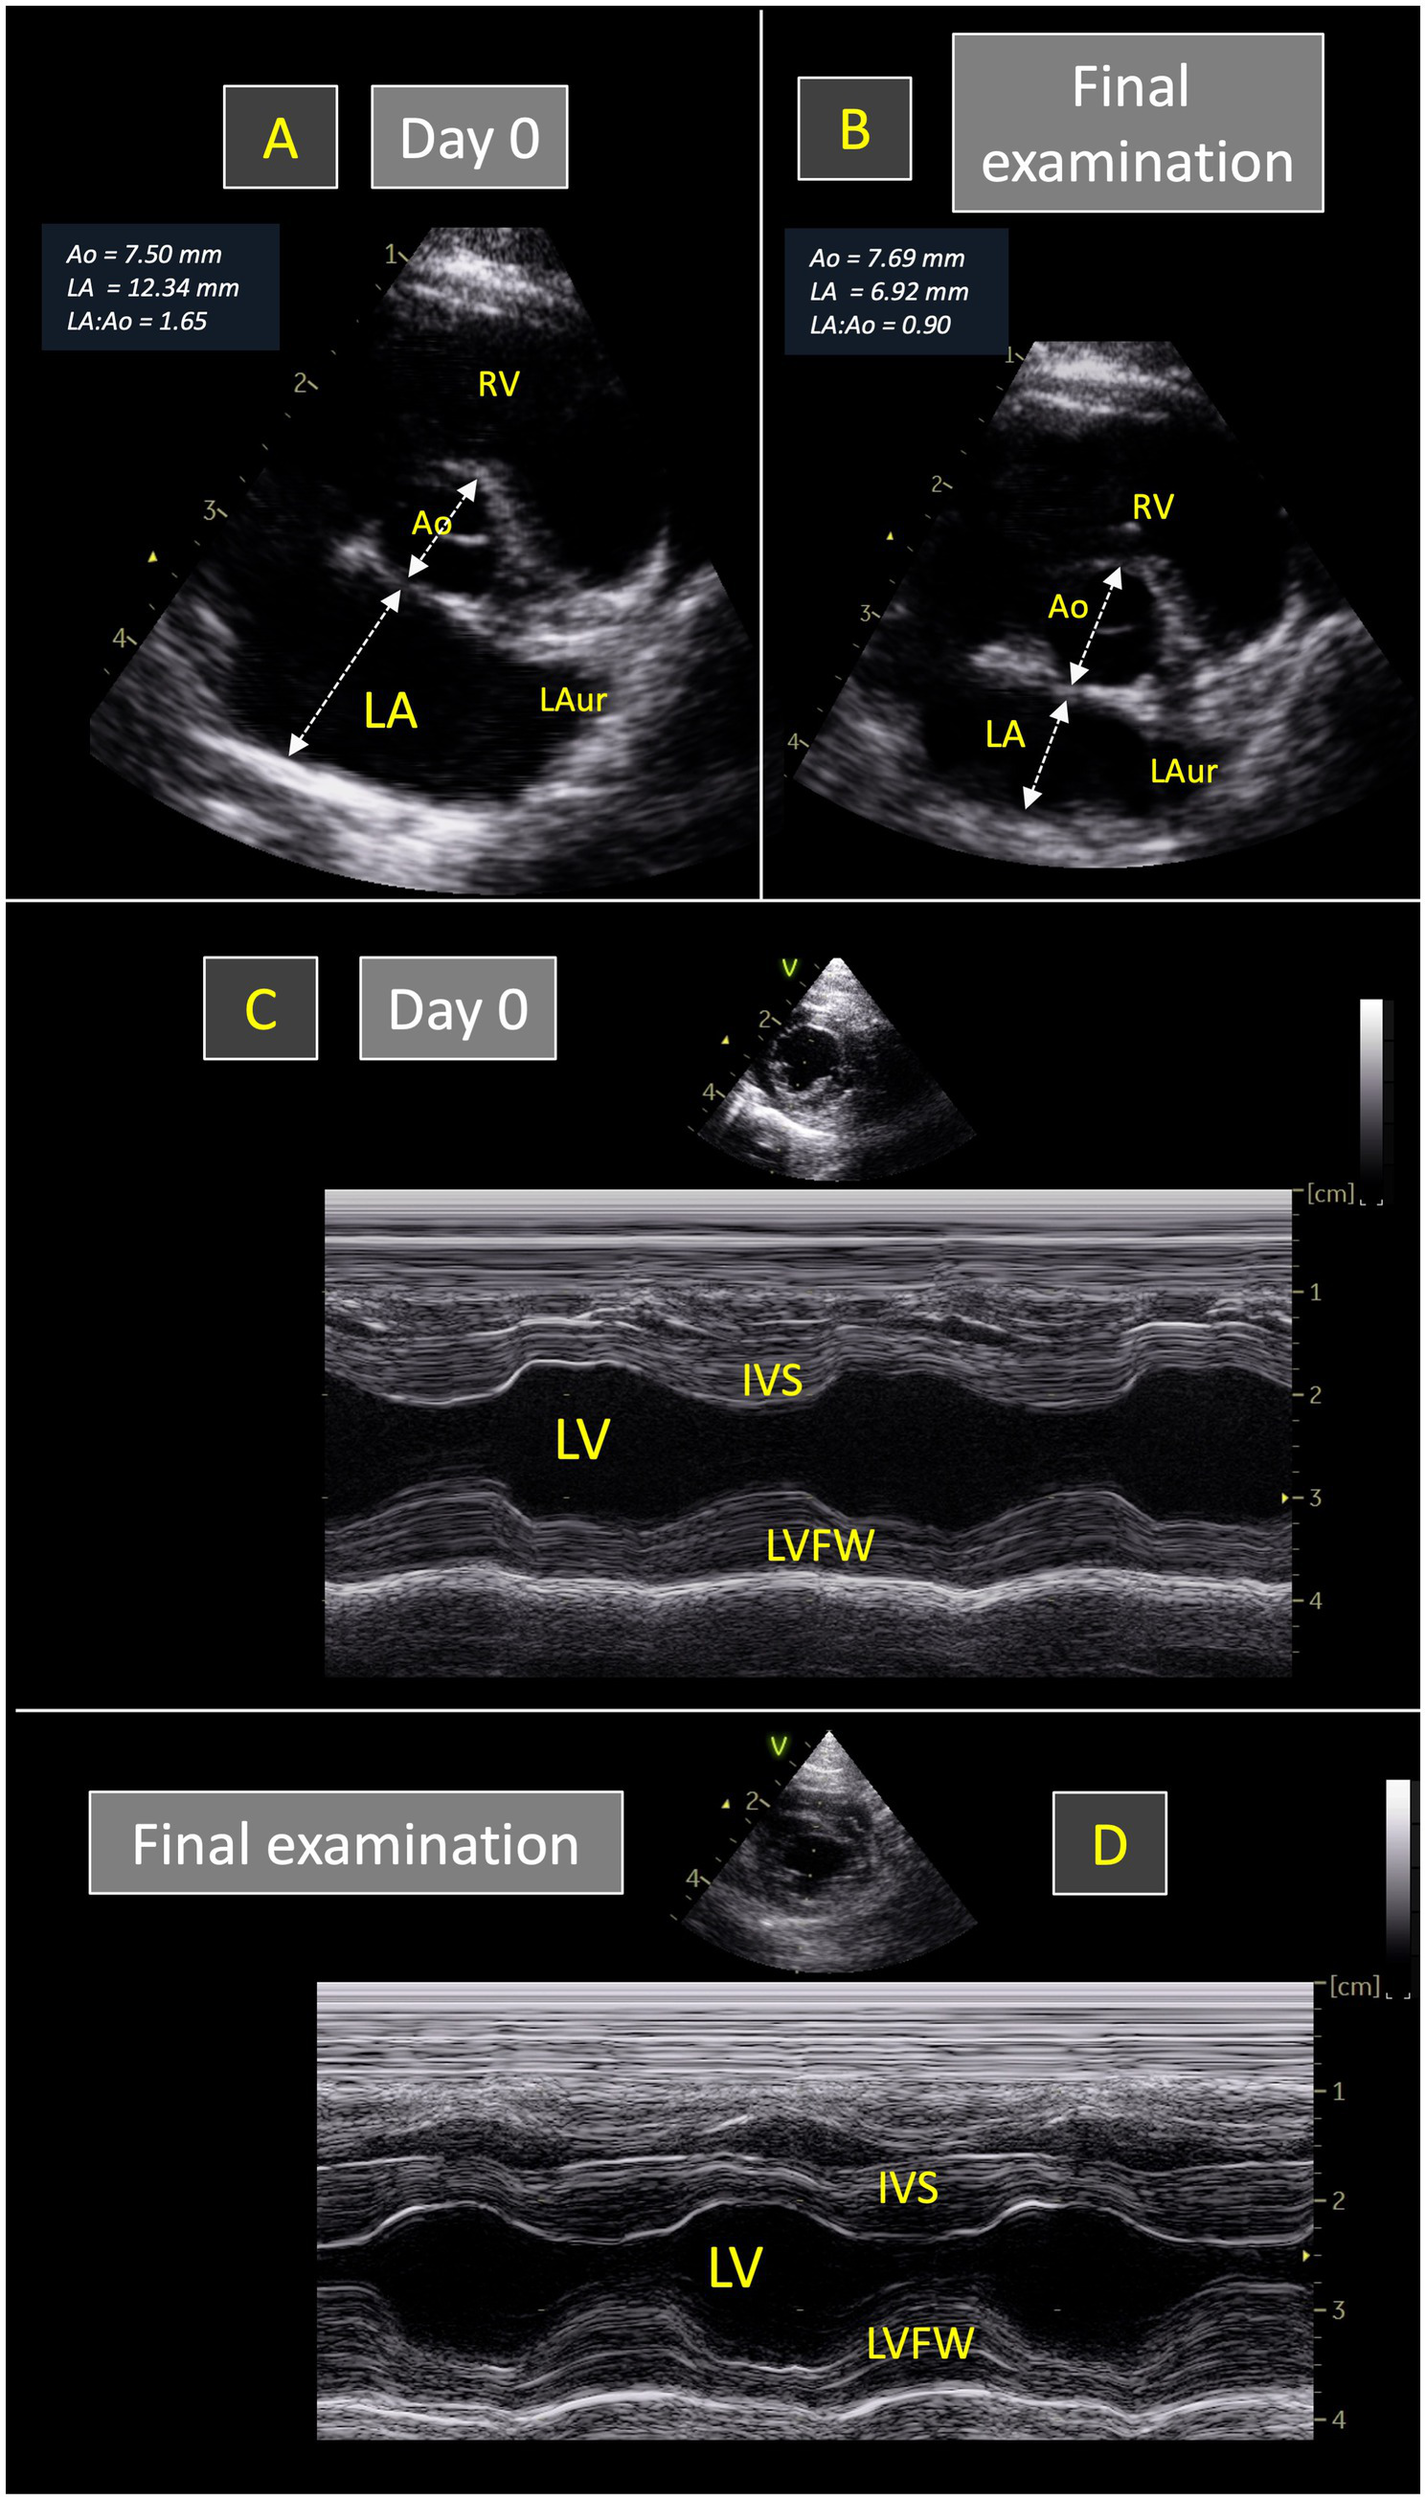

Figure 1

Representative echocardiograms recorded in one 3.5-kg cat with transient restrictive cardiomyopathy phenotype (from the TRCM group of the present study) at initial presentation (Day 0) and at final examination (35 days later). Short-axis right sided parasternal views obtained at the level of the aortic valve at end-diastole (A,B) show that the left atrium-to-aorta ratio (LA:Ao) was increased at Day 0 (1.65; A) and normalized at the final examination (0.90; B). As shown in (C,D), left ventricular M-mode measurements remained within normal ranges at both examinations. IVS, interventricular septum. LAur, left auricle. LV, left ventricle. LVFW, left ventricular free wall. RV, right ventricle.

3.3 Follow-up data and survival

In the TRCM group, the median time from the RCM phenotype diagnosis to evidence of its echocardiographic resolution was 156 days [77–211 days; 14–453 days], with normalization of LA dimensions for all cats, as confirmed by both end-diastolic LA:Ao ratio and Max LAD within normal ranges (Table 2). The final median end-diastolic LA:Ao ratio of TRCM cats was 0.97 (0.89–1.06; 0.77–1.14) vs. 2.01 (1.63–2.58; 1.37–3.0) in the NT-RCM group (p < 0.001, Figure 1), and the final median Max LAD was 12.0 mm (10.4–14.5 mm; 9.9–15.0 mm) vs. 23.4 mm (21.7–23.8 mm; 21.6–24.9 mm) in the NT-RCM group (p = 0.003). Similarly, the right atrial dilation initially identified in 8/17 TRCM and 11/16 NT-RCM cats disappeared in all TRCM cats, while it remained dilated in all NT-RCM cats (Table 2). Additionally, the mitral E:A ratio normalized in all TRCM cats (1.25 [1.15–1.60; 0.79–1.95]), which was not the case for NT-RCM cats (3.0 [2.98–4.24; 2.28–6.0]; p < 0.001). Lastly, LV thicknesses and LV diameters remained within normal ranges for all TRCM and NT-RCM cats at the final examination and was not significatively different within and between each group.